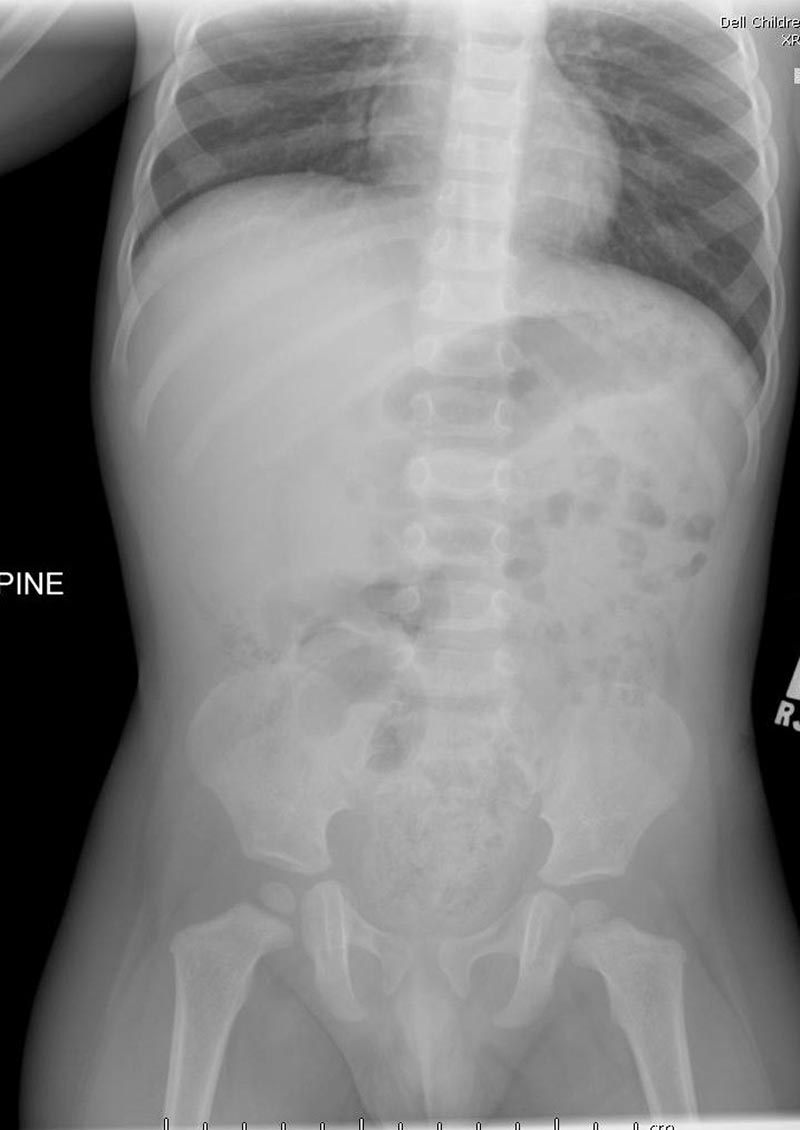

10-month-old male infant presents to the ED by EMS with vomiting and altered mental status (AMS). Infant arrives to the ED awake but poorly interactive. Ultimately, the infant will be diagnosed with intussusception and hypovolemic shock based on the history, physical exam and ultrasound findings. Learners are expected to establish a differential diagnosis of AMS appropriate for an infant, demonstrate appropriate resuscitative interventions, and use appropriate imaging and labs to help identify the cause of AMS.